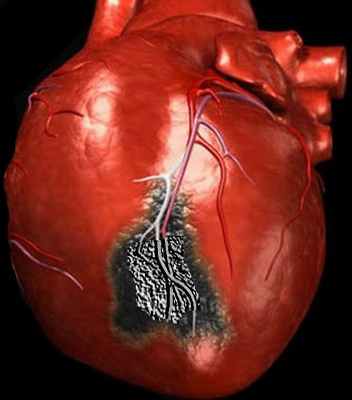

Результаты аутопсии подтвердили диагноз трансмурального инфаркта миокарда в базальных и средних сегментах передней стенки ЛЖ с площадью поражения миокарда 16 процентов с вовлечением передней папиллярной мышцы и ее полным разрывом.